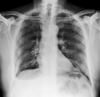

• Обычно проводят рентгенографическое исследование грудной клетки

Пальпация грудной стенки может выявить наличие нескольких переломов ребер. Некоторые врачи считают, что сбора анамнеза и физикального обследования достаточно при диагностике здоровых пациентов с незначительными травмами. Тем не менее, для пациентов с клинически значимой тупой травмой обычно проводят рентгенографическое исследование грудной клетки, с целью выявления сопутствующих травм (например, пневмоторакса, ушиба легких). Многие переломы ребер не заметны на рентгенограммах грудной клетки; в этих случаях могут быть проведены специфические исследования визуализации ребер, но идентификация всех случаев переломов ребер с использованием рентгенографии не является необходимой. Для выявления сопутствующих травм, которые подозреваются на основе клинических данных, проводятся другие диагностические тесты, такие как КТ-сканирование.